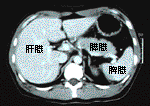

肋骨(ろっこつ)の下の部分を下から撮影。臓器の内部のようすもわかる。周囲の黒い部分は脂肪

従来の画像診断の代表は、X線でした。X線は、体の正面から撮影し、診断する方式のものです。胃や肺などの臓器の全体をとらえることができます。ただ、正面からとらえることしかできないので、骨の陰にある異常を見つけることが困難でした。

CT検査はX線を利用して、体を横に輪切りにして画像を撮ることができます。この検査法の開発により、画像診断が大きく進歩しました。